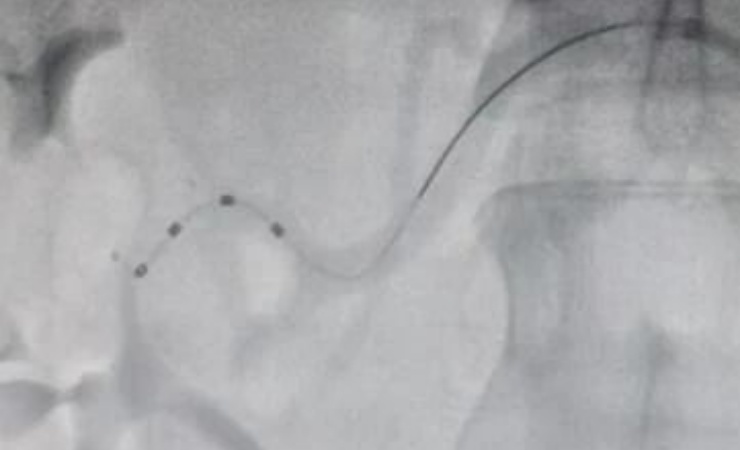

术前,副院长范晓涌,北大人民医院教授王伟民与心内科主任佟勤红及科室相关人员召开病例讨论会,决定对患者进行RDN高血压介入手术治疗。选择股动脉路径进行穿刺,在导丝引导下将Symplicity Spyral消融导管送至消融的部位并分别进行消融,消融双肾主干及分支部位65个点位,对双侧的肾动脉进行了全面、完整的消融。整个手术过程耗时1小时。消融后肾动脉无痉挛、狭窄、夹层等并发症,手术获得圆满成功。鉴于RDN治疗效果最佳观察期为术后3个月,故目前继续服用降压药物治疗,后续将对患者进行密切随访观察,根据血压情况进一步调整治疗方案。